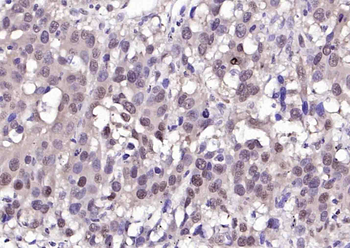

50 μl, 100 μl - MARK3 Recombinant Rabbit Monoclonal Antibody [orb704310]Featured

ICC, IF, IHC-Fr, IHC-P

Human, Mouse

Rat

Rabbit

Recombinant

Unconjugated

50 μl, 100 μl - Featured